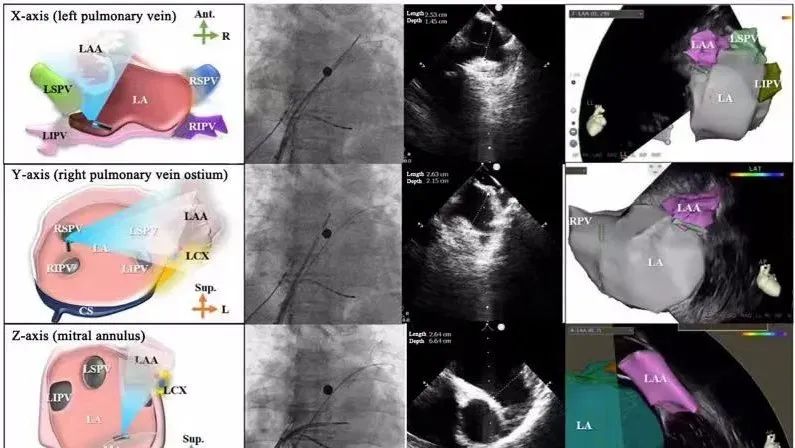

一種與心導(dǎo)管檢查相結(jié)合的超聲心動圖診斷新興技術(shù),通過將超聲探頭置于心腔內(nèi)部,發(fā)射并接收超聲信號,來精確獲取心臟解剖結(jié)構(gòu)、心臟血流動力學(xué)等信息的實(shí)時成像。與其他影像技術(shù)相比,ICE技術(shù)具有操作簡單、無輻射、安全性高、手術(shù)效率高、實(shí)用等優(yōu)勢,ICE在很大程度上有望取代經(jīng)食道超聲心動圖(TEE),成為電生理和結(jié)構(gòu)性心臟病領(lǐng)域的理想成像方式。

目前ICE技術(shù)已被應(yīng)用于左心耳封堵、房顫射頻消融、二尖瓣成形、房間隔缺損封堵等多種心臟介入手術(shù),應(yīng)用場景主要圍繞心臟電生理、結(jié)構(gòu)性心臟病等領(lǐng)域,目前以電生理應(yīng)用為主。數(shù)據(jù)顯示,我國結(jié)構(gòu)性心臟病介入器械市場規(guī)模已從2017年的4億元增長至2021年的20億元,年復(fù)合增長率達(dá)48.3%;預(yù)計到2025年,該市場規(guī)模將達(dá)到104億元,可以預(yù)見ICE市場規(guī)模也將同步高速增長,未來市場發(fā)展空間廣闊。

心腔內(nèi)超聲(ICE)技術(shù)壁壘極高,國內(nèi)主要廠商核心部件仍舊為進(jìn)口,集成了超聲和圖像處理最前端技術(shù),包括超聲探頭、線纜、軟件成像算法等,是當(dāng)前內(nèi)窺超聲方向最具挑戰(zhàn)的領(lǐng)域。ICE的應(yīng)用經(jīng)歷了2D平面成像、3D三維立體成像、以及4D的實(shí)時三維立體成像階段。